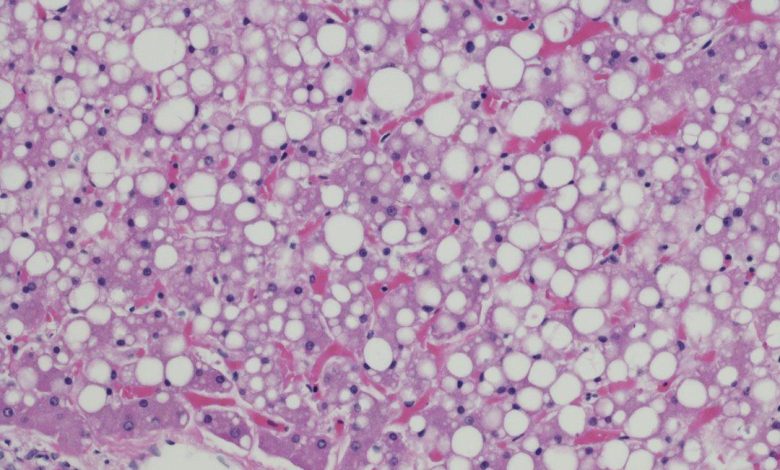

Estudos recentes revelaram que aproximadamente 30% da população global sofre com o acúmulo de gordura no fígado, conhecido como esteatose hepática. Essa condição, muitas vezes associada a uma dieta rica em gorduras e açúcares, além do sedentarismo, pode desencadear complicações sérias, como diabetes tipo 2, hipertensão e colesterol elevado. A gordura em excesso no fígado prejudica suas funções vitais, como a filtragem do sangue, a eliminação de toxinas, o metabolismo de medicamentos, a quebra de gordura, a produção de proteínas e a regulação da coagulação. Quando não tratada, a esteatose hepática pode evoluir para quadros mais graves, como hepatite gordurosa, cirrose hepática e até câncer de fígado. Fonte:metropoles